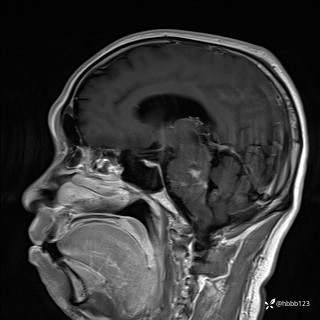

患者男,51岁。

简要病史:患者自述于1周前至某人民医院发现脑干肿瘤(具体不详),为求进一步诊断至我院就诊。

完善颅脑MRI平扫+增强,颅脑CT平扫:

T1增强矢状位重建: